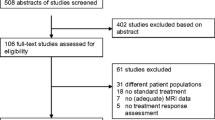

Studies in categories D were excluded based on title only. Studies in groups A, B, C were reassessed for compliance with the inclusion and exclusion criteria by screening their abstracts. The full text was consulted in unclear cases (Fig. 1).

Workflow of the study search and selection. Two databases were searched using the predefined search strategy—MEDLINE, Medical Literature Analysis and Retrieval System Online (PubMed), and Web of Science database (WoS). After excluding the duplicates the studies were initially screened by title (excluding n = 446 studies), abstract (excluding n = 96 studies), and full text (excluding n = 25 studies), leaving 60 studies. Six more studies were discovered by screening the reference sections of selected studies

The search resulted in 746 records of which 70 studies were eligible for review (Fig. 1).